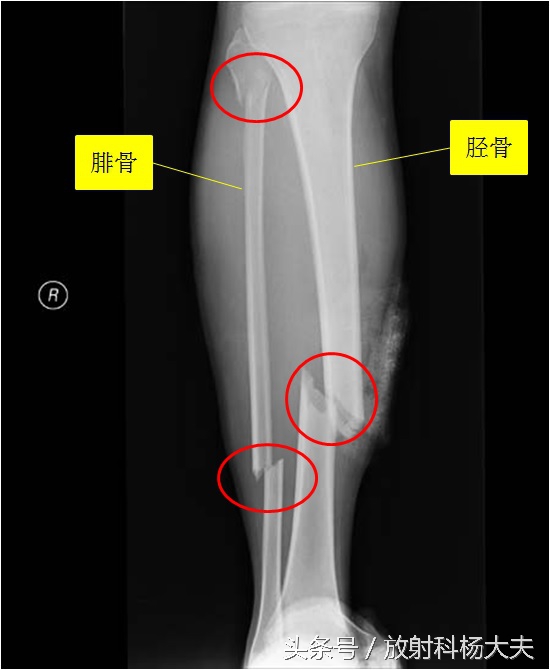

对于骨折,X线片是首选的诊断,比如下面一图为胫腓骨骨折,胫骨和腓骨均有多条透亮线。